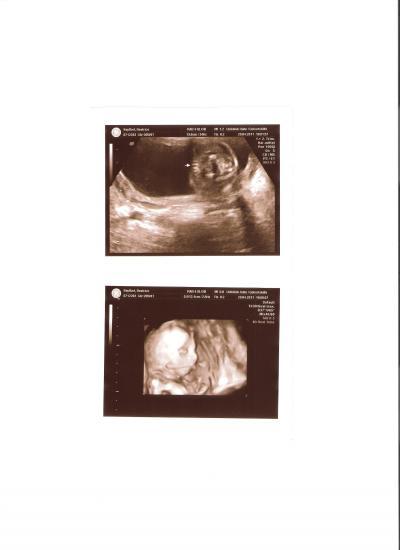

Hi Mädels, hatte heute meine Feinsono. Alles super mit dem Baby. Bin überglücklich!!! Hier einige Daten, wenn ihr vergleichen wollt. BPD 47,8mm FOD 61,7mm KU 17,31 cm AU 15,64cm FL 3,40 cm / Größe des Babys 23,8cm HL 3,10 cm geschätzes Gewicht 368g und das beste ist: ES BLEIBT ZU HUNDERT PROZENT EIN MÄDCHEN

Bild zu Endlich Gewissheit!!! Juhu!!! - Forum für September - Mamis